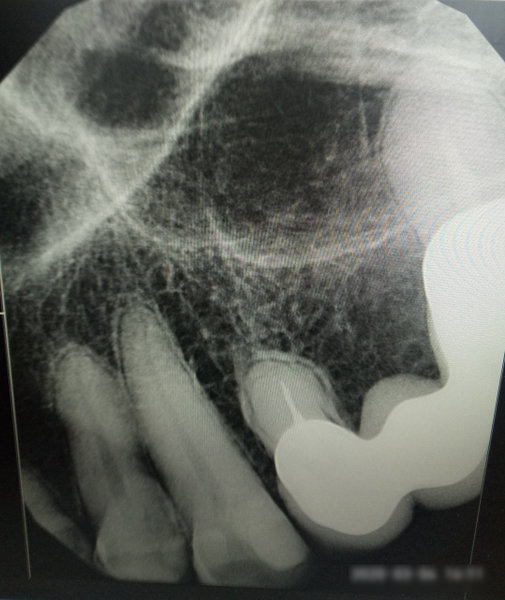

В данном зубе имеются три очевидные проблемы:

• имеется воспаление на верхушке корня (периодонтит), который подлежит лечению перед установкой вкладки;

• наблюдаются изменения по бифуркации;

• начальная стадия кариеса корня.

Все симптомы говорят о том, что необходимо сменить доктора и более внимательно и качественно отнестись к лечению данного зуба. Необходим детальный развернутый снимок с разных ракурсов. Необходимо сейчас обратиться к врачу и лечить обострение периодонтита и только потом заниматься протезированием. В противном случае данный зуб вы можете потерять.